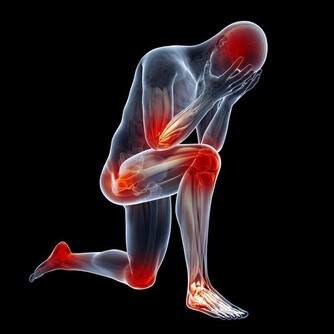

具有降低血壓、養陰清熱的功效,患高血壓、心髒病、肝炎、肝硬化的病人,經常喝些紅酒大有益處。

紅酒有助於腎臟排泄尿酸和預防痛風、風濕病和關節炎。